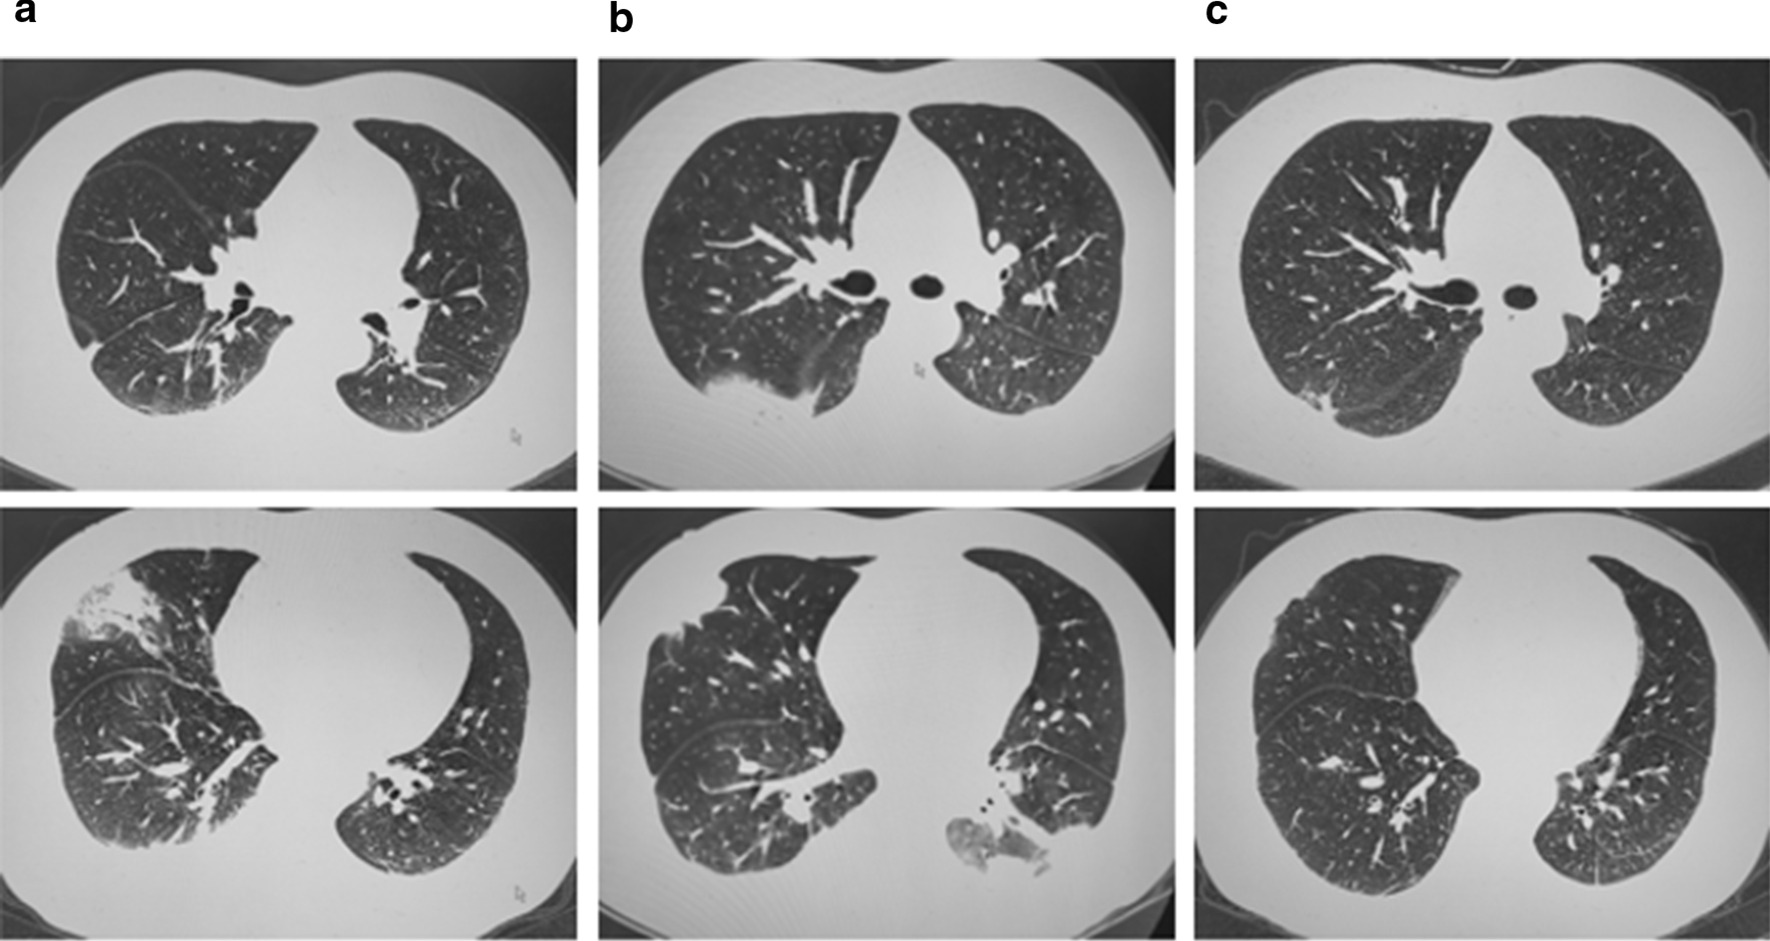

Fig. 1.

Chest CT scan (a). Upon arrival: chest CT imaging suggested pulmonary infection with pleural effusion (b). Seven days after admission: chest CT imaging suggested more extensive pulmonary infection with pleural effusion (c). Seventy days after admission: signs of lung infection were dramatically improved, and pleural effusion was also obviously absorbed

He denied a history of hypertension, diabetes, coronary heart diseases, or infections such as hepatitis B and tuberculosis. Relevant laboratory findings were as follows: white blood cell: 13.54 * 109/L (reference interval: 3.50–9.50 * 109/L); neutrophil%: 87.1% (RI: 40.0–75.0%); lymphocyte%: 10.2% (RI: 20.0–50.0%); hypersensitive C-reactive protein: 92.9 mg/L (RI: < 1 mg/L); D-dimer: 1.37 µg/ml (RI: < 0.5 µg/ml). Influenza and parainfluenza IgM antibodies were tested, and the results were negative. No obvious abnormalities were found on an electrocardiogram or for the rheumatic immune system, routine urine and liver function, electrolyte or renal function. Fibreoptic bronchoscopy and sputum smear did not show any abnormalities. Chest CT imaging suggested pulmonary infection with pleural effusion (Fig. 1a), which was confirmed by pleural ultrasonography. Therefore, he continued to be treated for severe community-acquired pneumonia.

Two days after admission, he developed a fever with a temperature of 37.5 °C, with no relief of chest pain. Given this, we considered the possibility of tuberculosis. However, no acid-fast bacilli were found in sputum smears or by T-SPOT. A TB test was nonreactive. The results of gene X-pert and acid-fast staining along with that of tuberculous culture, which was obtained a few days later, were all negative. Seven days after admission, his chest pain significantly worsened. Enhanced chest CT imaging showed bilateral pulmonary embolism of the secondary pulmonary artery and its far branch, bilateral pleural effusion, and atelectasis of the lower lobe in the bilateral lungs (Fig. 1b). CT-pulmonary artery angiography one day later revealed similar results (Fig. 2). We also noted an elevation of D-dimer up to 3.51 µg/ml. We therefore performed echocardiography and deep venous sonography to detect cardiac diseases and deep vein thrombosis, respectively, with no positive results.

We faced a clinical dilemma regarding his diagnosis and treatment; one day later, Absidia was detected in bronchoalveolar lavage fluid culture, which provided us with guidance for subsequent treatment. Given that he was a warehouse keeper and acknowledged a history of inhaling dust in the warehouse, we speculated that he may be infected by inhaling fungal spores attached to dust. Given that such fungi can invade the brain and sinuses, a CT scan of these organs was performed rapidly and showed no damage. Antifungal therapy with oral posaconazole and intravenous amphotericin B was started immediately. The patient was given 400 mg posaconazole and 10 mg amphotericin B on the first day followed by 20 mg amphotericin B daily as maintenance therapy. Unsurprisingly, his symptoms, such as chest pain and cough, were relieved, and his temperature returned to normal. Furthermore, chest CT re-examination showed dramatic improvement in the signs of lung infection; the pleural effusion was also obviously absorbed (Fig. 1c). During follow-up for two years after discharge, he was completely cured without any recurrence or sequelae.